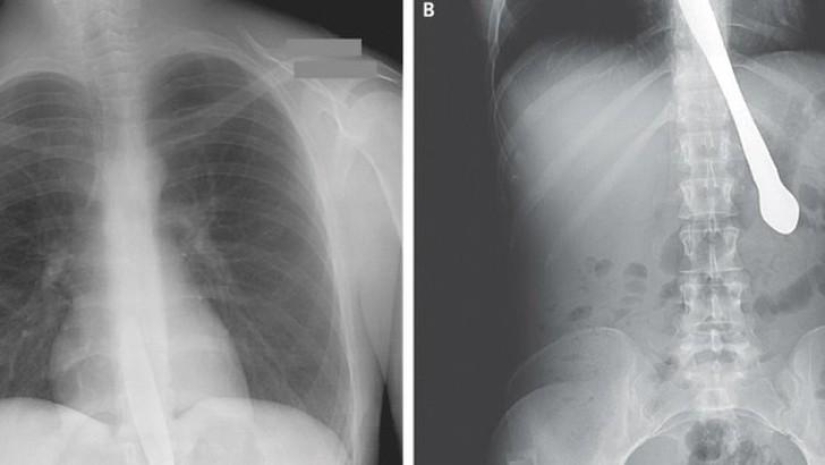

Bala.

Hélice de avión.